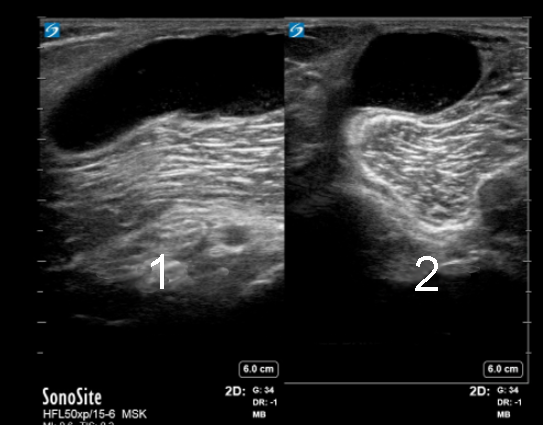

Posterior Medial Knee Baker's Cyst

Longitudinal

Transverse